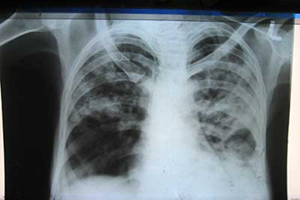

Chest and Tuberculosis (TB)

TB is caused by the bacterium Mycobacterium tuberculosis (M tuberculosis). TB is contagious. This means the bacteria is easily spread from an infected person to someone else. You can get TB by breathing in air droplets from a cough or sneeze of an infected person. The resulting lung infection is called primary TB.

TB can affect any organ system, although manifestations are most commonly related to the chest. The lungs are the most common and often the initial site of involvement. Chest involvement is most commonly pulmonary, followed by lymph nodal and pleural disease (latter two are included under EPTB). Chest wall, cardiac, breast, and skeletal involvement can also occur in the thorax.

The goal of treatment is to cure the infection with medicines that fight the TB bacteria. Active pulmonary TB is treated with a combination of many medicines (usually four medicines). The person takes the medicines until lab tests show which medicines work best.

In most Hospital, only active TB is treated due to lack of resources. In Globira Medical Services, you can also choose treatment to reduce your risk of developing active TB, which can affect your academic and life goals.

All of our doctors are fully trained and board-certified. Our mission is to provide quality health care to patient and an understanding of health issues.